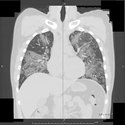

HRCT :

Ground-glass opacification, predominantly in a homogeneous distribution.

Thickened intralobular structures and interlobular septa in typical polygonal shapes, referred to as "crazy-paving“